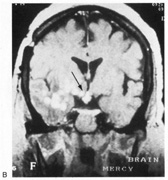

Achromatopsia in the contralateral hemifield alone can follow unilateral right or left occipital lesions (Fig. 18). Patients are typically asymptomatic until the defect is demonstrated on examination.234,235 Hemiachromatopsia is usually associated with a superior quadrantanopia;234,235,241 therefore, the color defect is only demonstrable in the remaining inferior quadrant. The preserved color vision in the ipsilateral hemifield allows normal or near-normal performance on centrally viewed tests of color vision such as pseudoisochromatic plates. The incidence of hemiachromatopsia is probably underestimated, given its asymptomatic nature and the failure of routine clinical color tests to detect its presence.

Fig. 18. Magnetic resonance imaging scan of patient with stroke causing a right hemiachromatopsia as well as partial superior quadrantanopia.